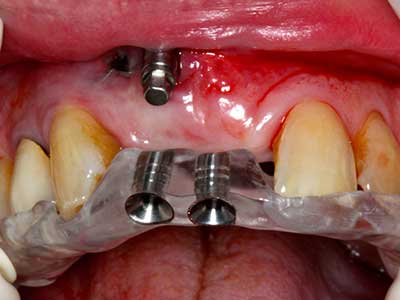

Indication: Preparations close to nerve tissue

Indication: Apical resection

When surgical procedures are performed on bone in the immediate vicinity of sensitive structures such as blood vessels or nerves, rotary instruments pose a significant risk of iatrogenic injury. Piezoelectric devices can be helpful for preparation of bone covers and removal of hard tissue close to nerves, particularly for exposure of nerves after iatrogenic injury but also during nerve lateralization for resective and reconstructive procedures or implant placement (Fig. 17-20). Light contact between the piezotip and the nerve does not generally result in damage but proceeding incautiously with saw-like motions or attachments where a residual bone substrate remains may cause temporary or even permanent nerve damage. However, the risk of damage is considered to be substantially lower than when using saws or milling instruments (Pereira, Gealh et al. 2014).